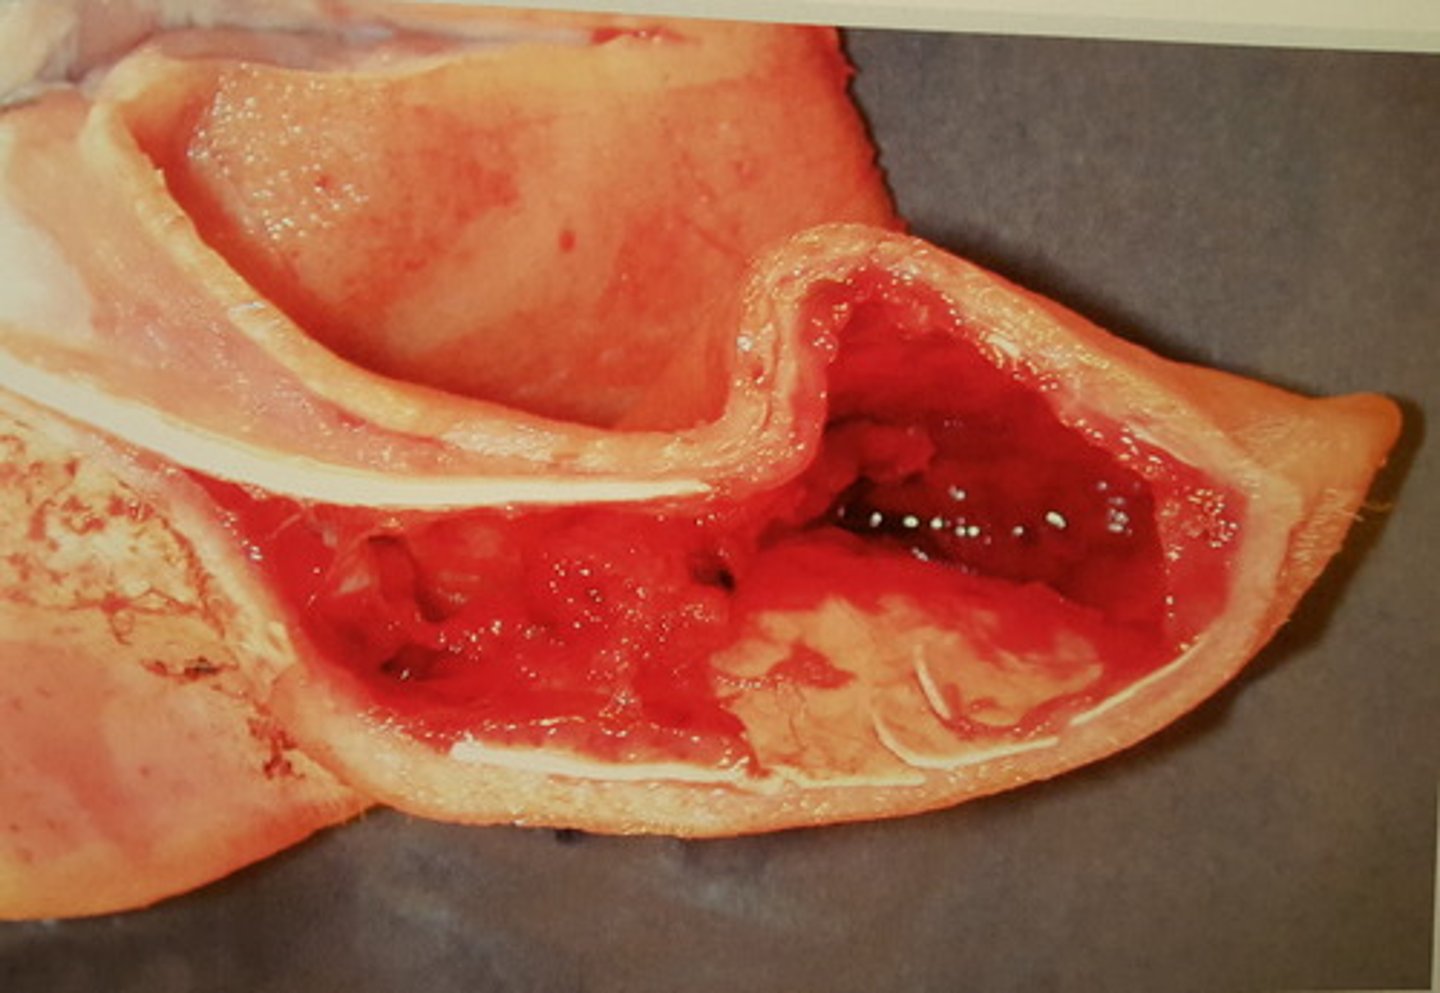

kolesterolgranulomer i plexus choroidei (lejlighedsfund). Kan give anledning til hydrocephalus

Hjerne fra hest. Patoanatomisk diagnose?